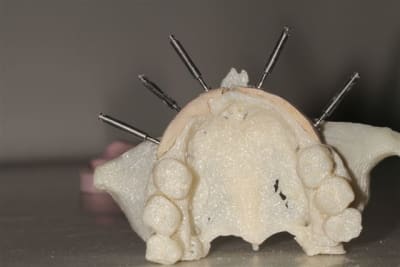

L’idée de base est d’obtenir un greffon adapté à la zone à greffer, et de donner plus de chance à la nature de faire son travail de reconstruction.

Dans un premier temps, les greffons sont préparés manuellement par votre serviteur, mais ensuite la machine outil prendra le relais, dés que seront résolus les petits problèmes d’environnement.

Une fois les greffons préparés, ils sont traités par un procédé spécifique à Biobank (CO2 supercritique) puis stérilisation (rayons gamma), et vous le verrez la pose devrait être extrêmement simplifiée.

La première diapo est un essai pour justifier le concept (os non destiné à une utilisation greffe)

la troisième et suivante ce sont "les greffons" définitifs.